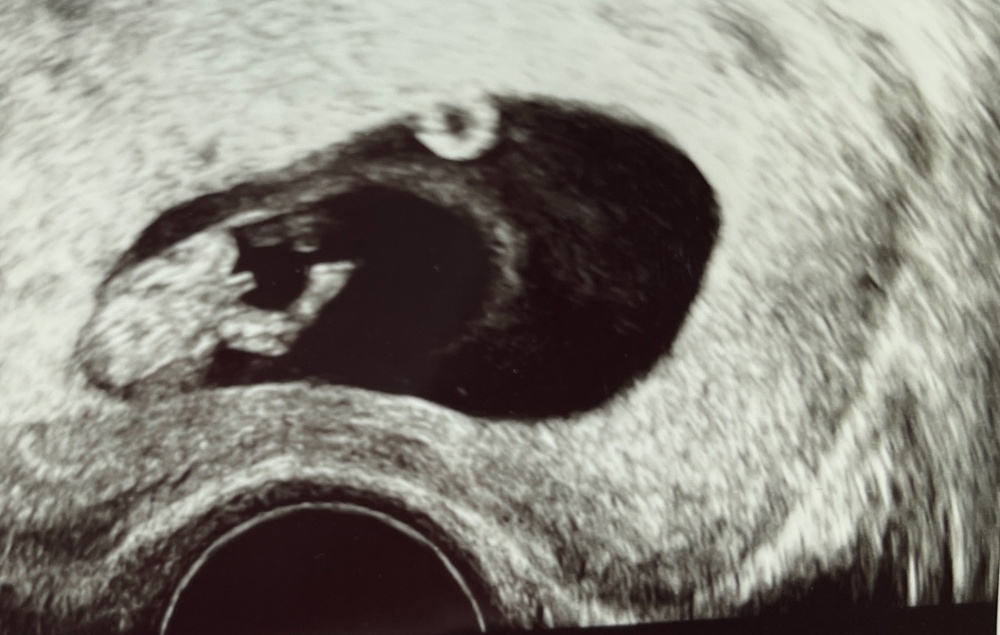

Wie auf Bild 1 sah bei uns der Bub aus ❤️